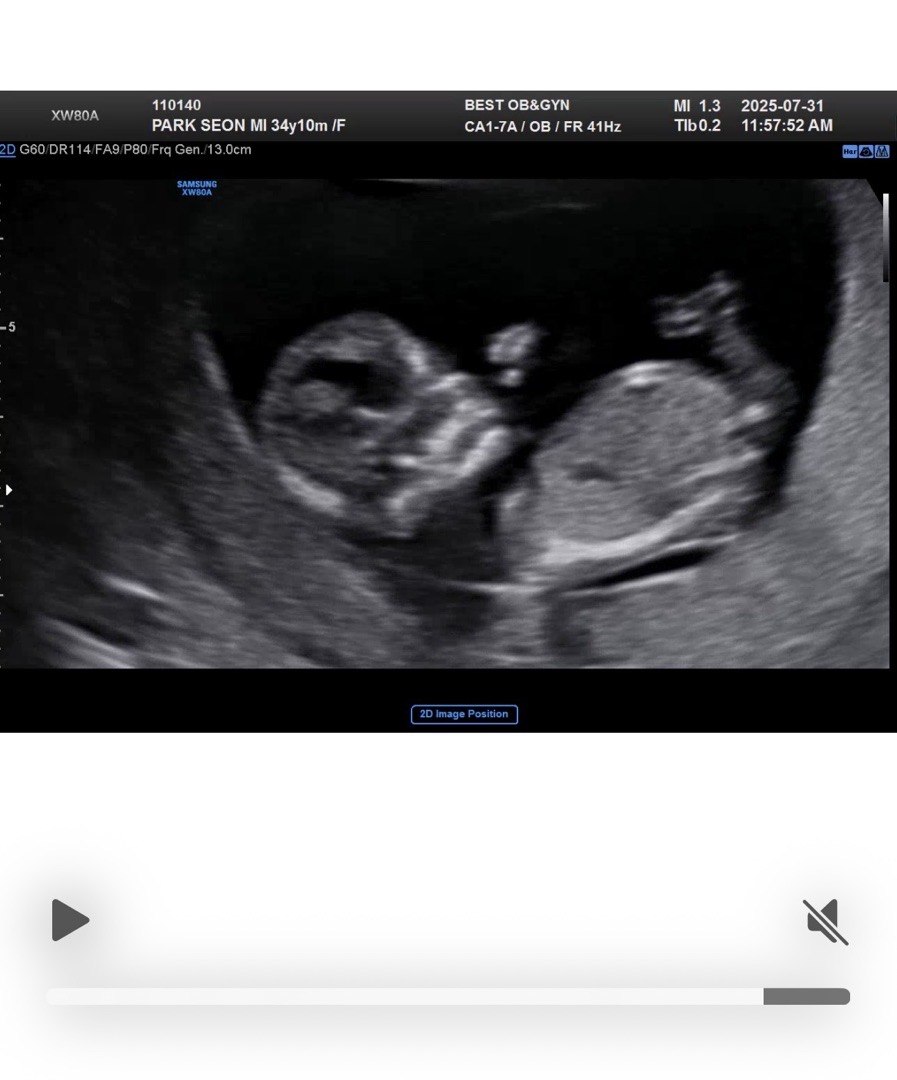

12주 3일차이고 오늘 1차 기형아 검사 받고 왔어요! 사진만 봤을때는 딸일까요 아들일까요? ㅎㅎ

생식기가 맞는지 애매해서 모르겠는데 아들 같아요!